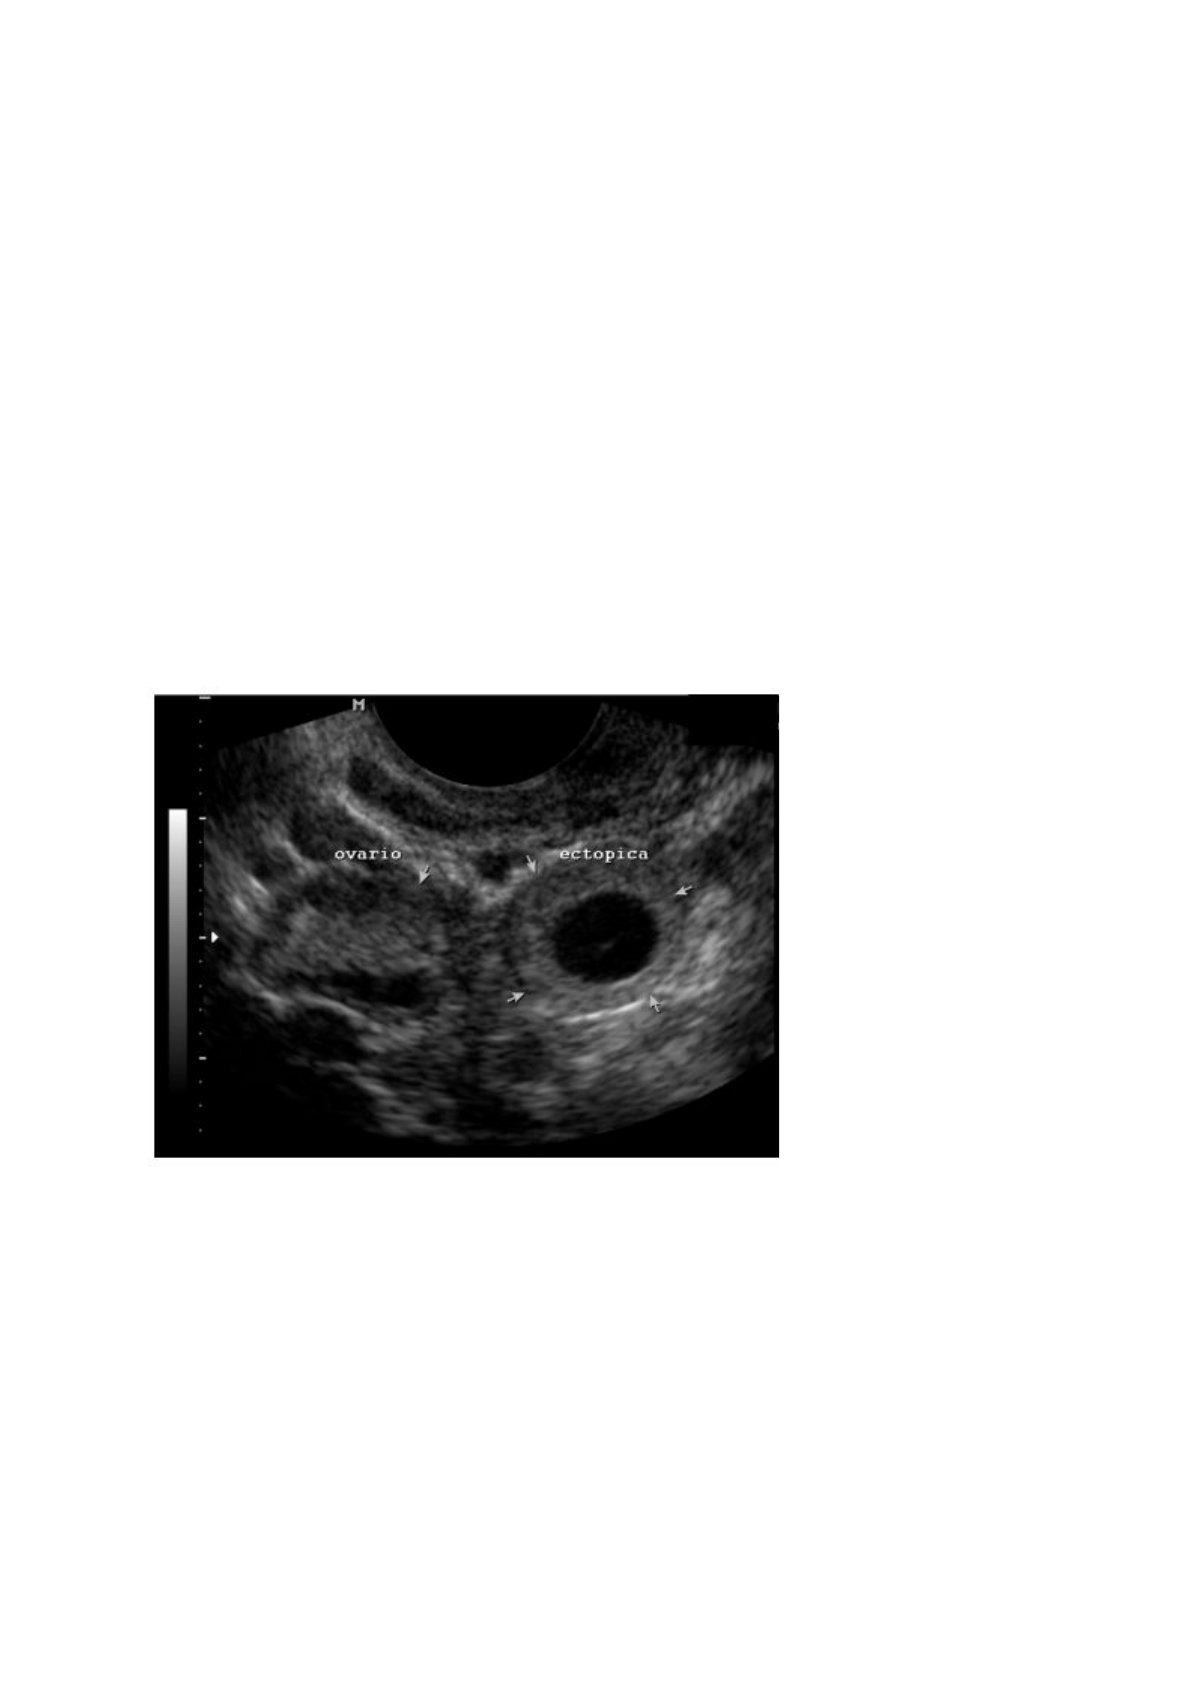

Gravidez Ectópica

Definição: Qualquer gravidez que ocorre fora da cavidade endometrial - inclusive no

estroma do útero, por exemplo. Não basta estar no útero! Precisa estar ​implantado ao

endométrio.

beta-HCG > 1500: + USG sem saco gestacional, vesícula vitelina, etc. = ​GE ectópica

Se beta HCG< 1500, com embrião fora da cavidade uterina, com BCF, também pode-se

afirmar que trata-se de GE.

Localização da GE

O principal local de implantação é a ​tuba uterina.